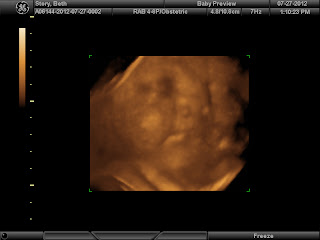

But in the meantime, here are some of the maternity photos we had taken as well as the 3D ultrasound shots that we also got.

This last picture (above) is the shot we got prints of right away to send to our parents and grandparents. These pics were taken on my birthday which was two days before we were officially at 37 weeks.

Everyone we've shown this picture to says that baby girl looks a lot like me. It will be interesting to see if she really looks that much like me when she's born.